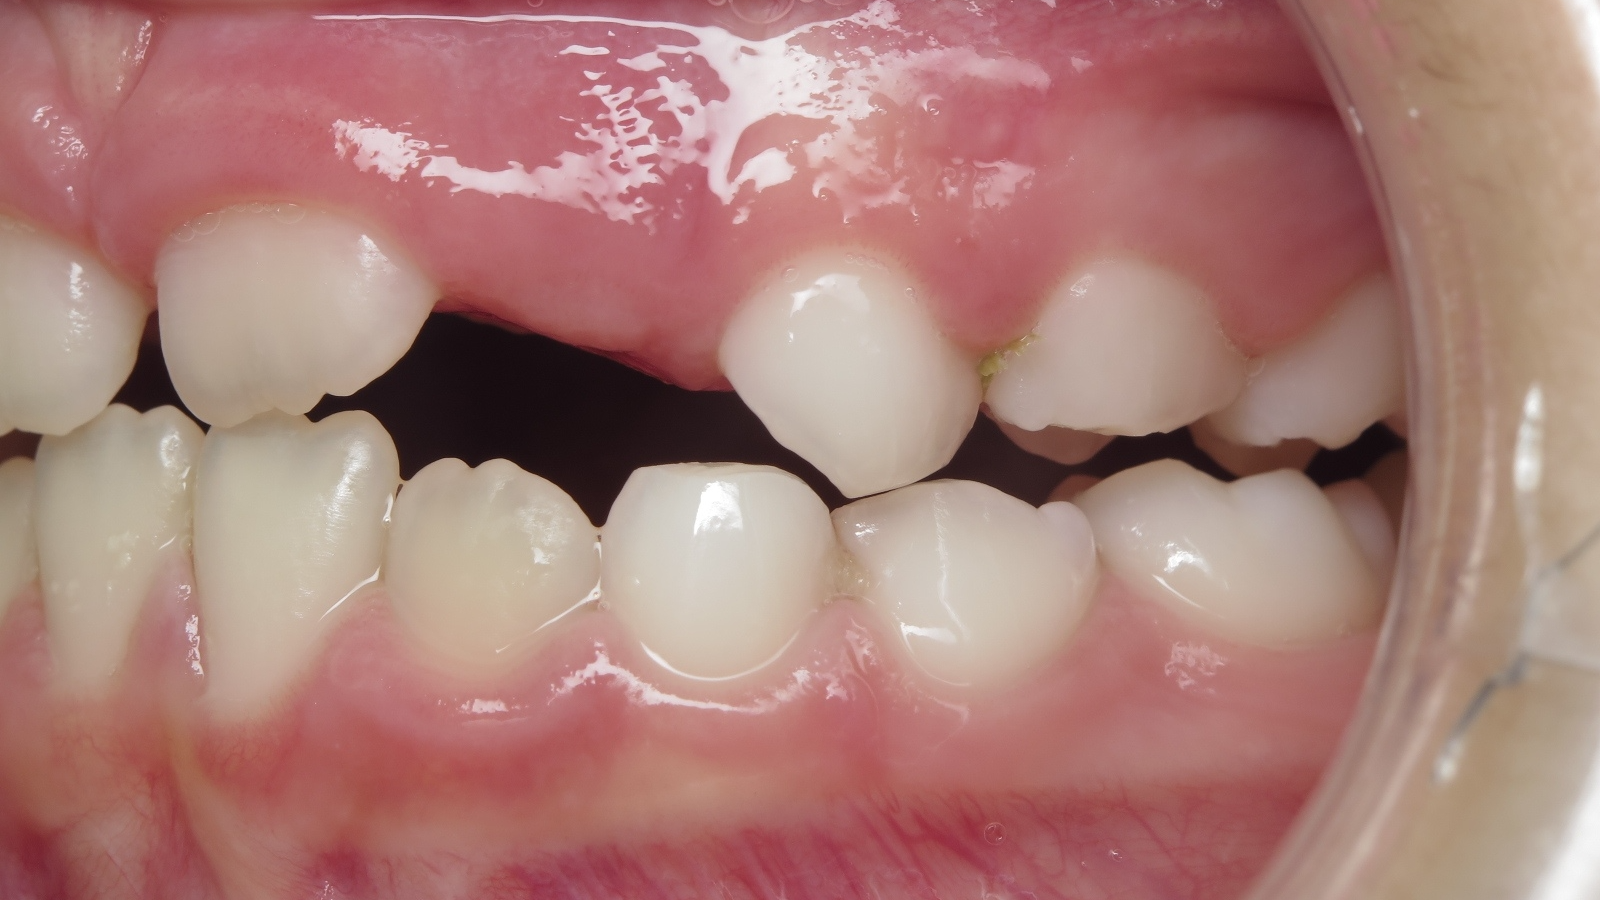

appareillage sectionnel multibagues pendant 18 mois

surveillance évolution de la dentition en cours

bilan début et en cours de traitement